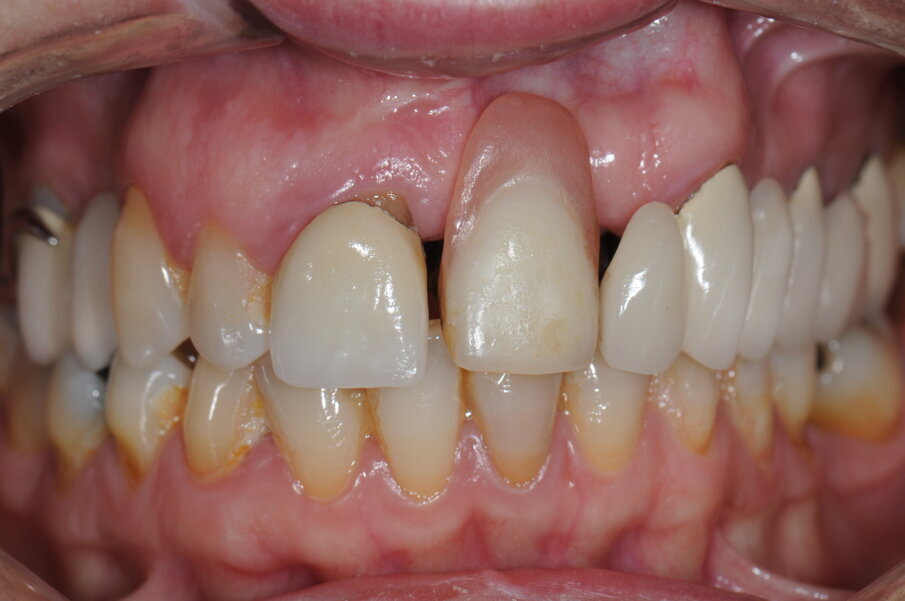

La paziente, donna, di anni 55, era giunta alla nostra osservazione richiedendo una riabilitazione protesica in area estetica a seguito di trauma provocato da un incidente stradale, avvenuto da circa 10 anni, che aveva determinando la perdita di due incisivi superiori in posizione 2.1, 2.2 (Figg. 1, 2).

La paziente ha categoricamente rifiutato queste soluzione di piano di trattamento, in particolare l’idea di un trattamento ortodontico e il rifacimento di precedenti restauri protesici. Richiedeva unicamente di trattare il settore frontale, esponendo gli operatori a un estremo e complicato compromesso. L’unico punto accettato è stato quello relativo alla necessaria estrazione dell’elemento 1.1 (molto compromesso dal punto di vista parodontale, preliminare alla tecnica di rigenerazione ossea) (Figg. 3, 4).

Fig. 2 - Visione frontale della zona edentula.